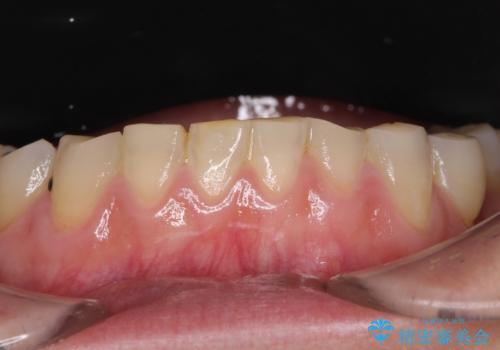

- 全顎的な歯肉からの出血と前歯の形態を気にして来院された患者様です。

診査の結果、上顎奥歯を中心に深い歯周ポケットが認められたため、歯周ポケット除去を目的とした歯周外科処置を行うこととしました。

歯周外科処置を行ったことで歯周ポケットはなくなり、毎回のブラッシングの度に嫌な思いをしていた出血は認められなくなりました。